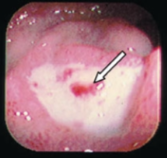

45yo male presents with two months of faecal frequency with loose stools, urgency and tenesmus. Associated with this is abdominal pain prior to defaecating and rectal bleeding

Ulcerative colitis